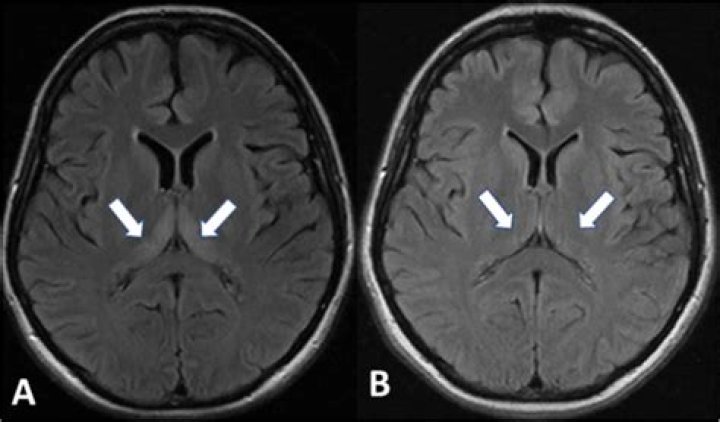

Does encephalopathy show up on MRI?

MRI is the imaging modality of choice and is often the first indicator of an encephalopathy as a possible cause of symptoms.